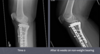

What is shown in these radiographs?

A

dystrophic mineralization at the level of an elbow joint repair